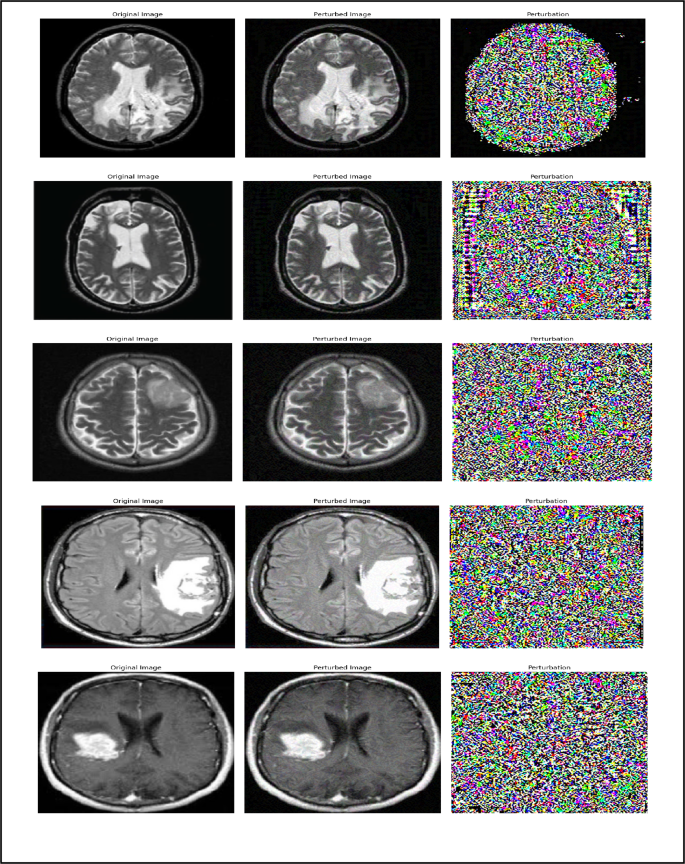

Adversarial attack methods

Research on adversarial attacks against machine learning models, particularly neural networks, has grown significantly, driven by the need to enhance their security and resilience26. Among the most widely used techniques for generating adversarial samples are Projected Gradient Descent (PGD) and the Fast Gradient Sign Method (FGSM). Both methods manipulate input data to deceive the model into producing incorrect predictions27, thereby exposing potential vulnerabilities28. Figure 2 illustrates normal MRI images, while Fig. 3 shows their perturbed counterparts generated using these adversarial techniques.

Normal MRI images.

Tumor MRI images.